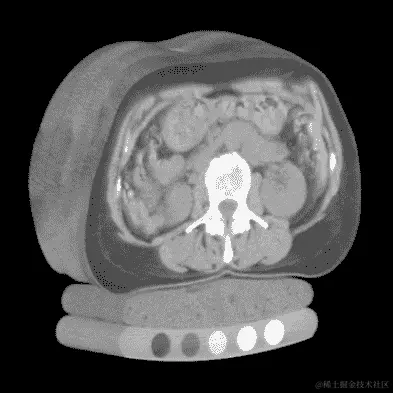

第 3 步(分组)将生成数据,第 4 步(分类)将消耗类似于图 9.6 中包含肿瘤顺序横截面的图像。这幅图像是(潜在恶性,或至少不确定)肿瘤的近距离视图,我们将训练第 4 步模型识别,并训练第 5 步模型将其分类为良性或恶性。对于未经训练的眼睛(或未经训练的卷积网络)来说,这个肿块可能看起来毫无特征,但在这个样本中识别恶性的预警信号至少比消耗我们之前看到的整个 CT 要容易得多。我们下一章的代码将提供生成类似图 9.6 的放大结节图像的例程。

图 9.6 CT 扫描中肿瘤的近距离、多层切片裁剪